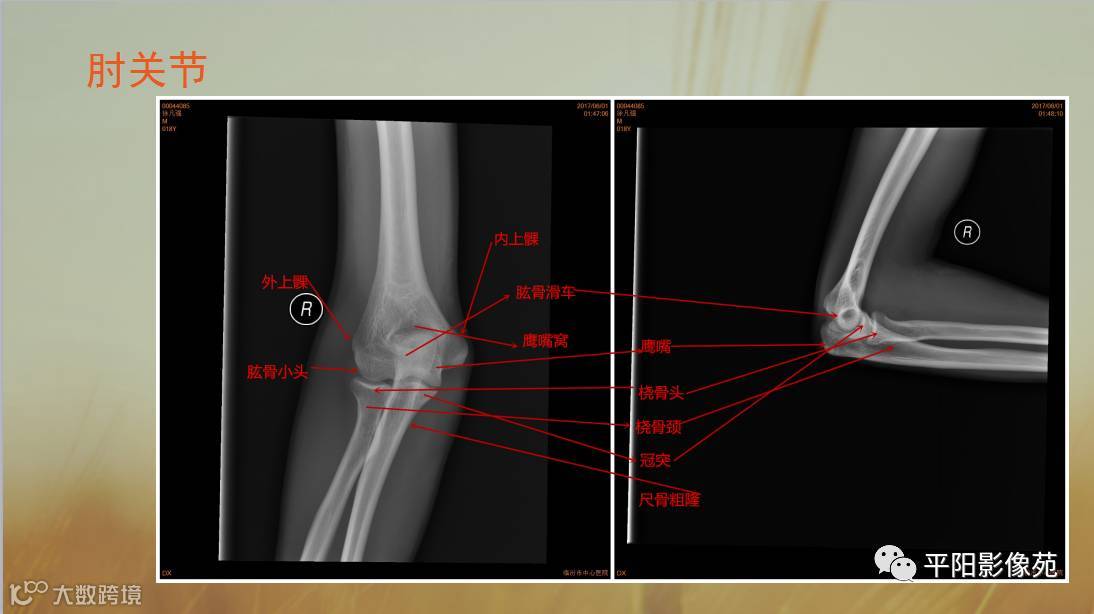

四肢骨骼X线解剖